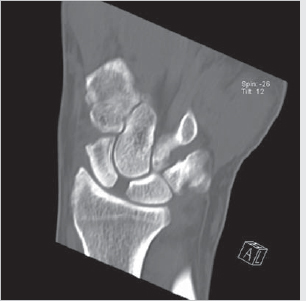

Scapholunate ligament tear

On X-ray and CT, can be seen as widening of scapholunate interval (► Fig. 4.5).

On MRI, T2 hyperintense (fluid bright) gap instead of expected T2 hypointense ligament.